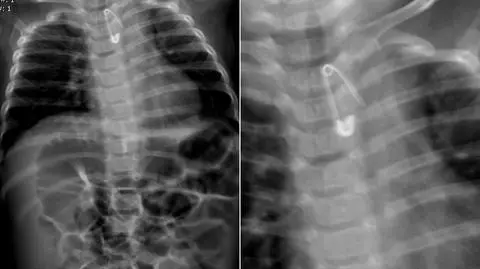

Dziecko połknęło agrafkę. Śledztwo prokuratury regionalnej w Łodzi